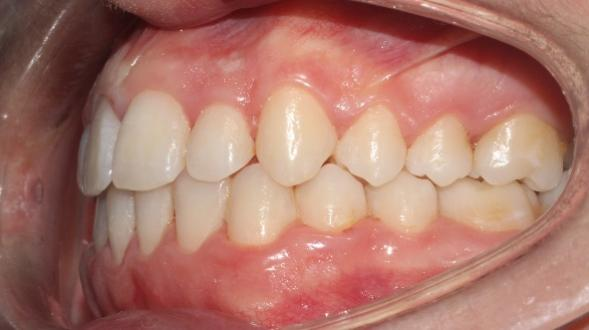

The patient in this case is a 15-year-old female who presented with mild third skeletal class with upper and lower tooth crowding at the beginning of the treatment. The whole process lasted for around 20 months employing traditional metal brackets.

Fig 1,2,3: the intraoral condition before orthodontics treatment & Fig 4,5,6: the intraoral condition after orthodontics treatment.